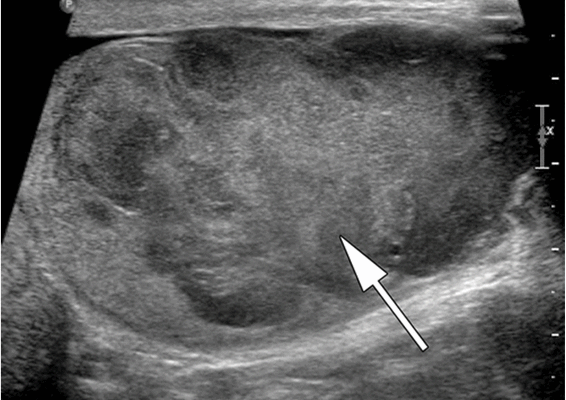

Ультразвуковое исследование (УЗИ) мошонки является предпочтительным начальным визуализирующим исследованием для оценки образования яичка. УЗИ может подтвердить наличие новообразования, определить его расположение и оценить состояние противоположного яичка (рис. 4). Чувствительность метода достаточно высокая - от 92 % до 98 %.

Снимок УЗИ яичка